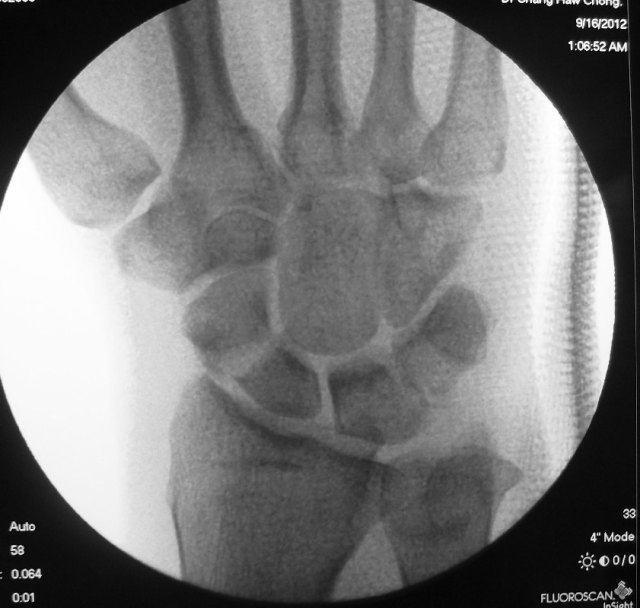

X-rays of his left wrist showed a fracture through the scaphoid bone of the wrist together with dislocation of the lunate bone. The diagnosis was a trans-scaphoid peri-lunate fracture dislocation.

There dislocation was immediately reduced under sedation and with fluroscopic confirmation.